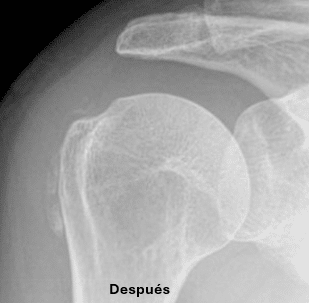

En la unidad de dolor del Instituto Valenciano de Ozonoterapia (IVO3T) la técnica que suele usarse es la punción y aspiración del hombro, técnica también conocida como Barbotaje, o sea un lavado ecoguiado de las calcificaciones en el hombro, esto consiste en la colocación de una aguja bajo anestesia local en el centro de la calcificación, de tal forma que mediante la inyección a presión de suero salino o anestésico se rompa la calcificación y se vacíe el material cálcico a la jeringa utilizada para el lavado.

La ruptura y fragmentación de las calcificaciones en el hombro depende en gran medida de la estructura de esta. Se consigue romper la calcificación en aproximadamente 2/3 de los casos seleccionados. En algunos casos no se consigue un vaciamiento de la calcificación dada su consistencia, en cuyo caso y siempre que la clínica persista, puede estar indicado su vaciamiento bajo control artroscópico.